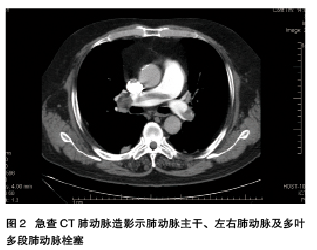

男性,66岁,因突发心前区疼痛1 d,分次含服硝酸甘油片10~12片,口服安定5片,疼痛持续不缓解,并出现头晕,到当地卫生院就诊,当时血压测不出,查心电图后予以输液,收缩压升至60 mmHg后转往我院,于2015年1月14日急诊收入我院CCU。患者既往有高血压病和慢阻肺病史。15日心脏超声示右心扩大,三尖瓣关闭不全(轻至中度),TI法估测肺动脉收缩压约68 mmHg,急查CT肺动脉造影示肺动脉主干、左右肺动脉及多叶多段肺动脉栓塞(图2),诊断急性肺栓塞(高危),予以溶栓治疗后,为进一步治疗,转入RICU。16日超声示左下肢股深静脉血栓形成。19日复查心脏超声示右房扩大,三尖瓣关闭不全(轻-中度),肺动脉扩张,肺动脉高压,TI法估测肺动脉收缩压约53 mmHg。29日复查超声示左下肢股浅静脉远端、腘静脉及其属支血栓形成。30日出院并继续口服华法林抗凝治疗。